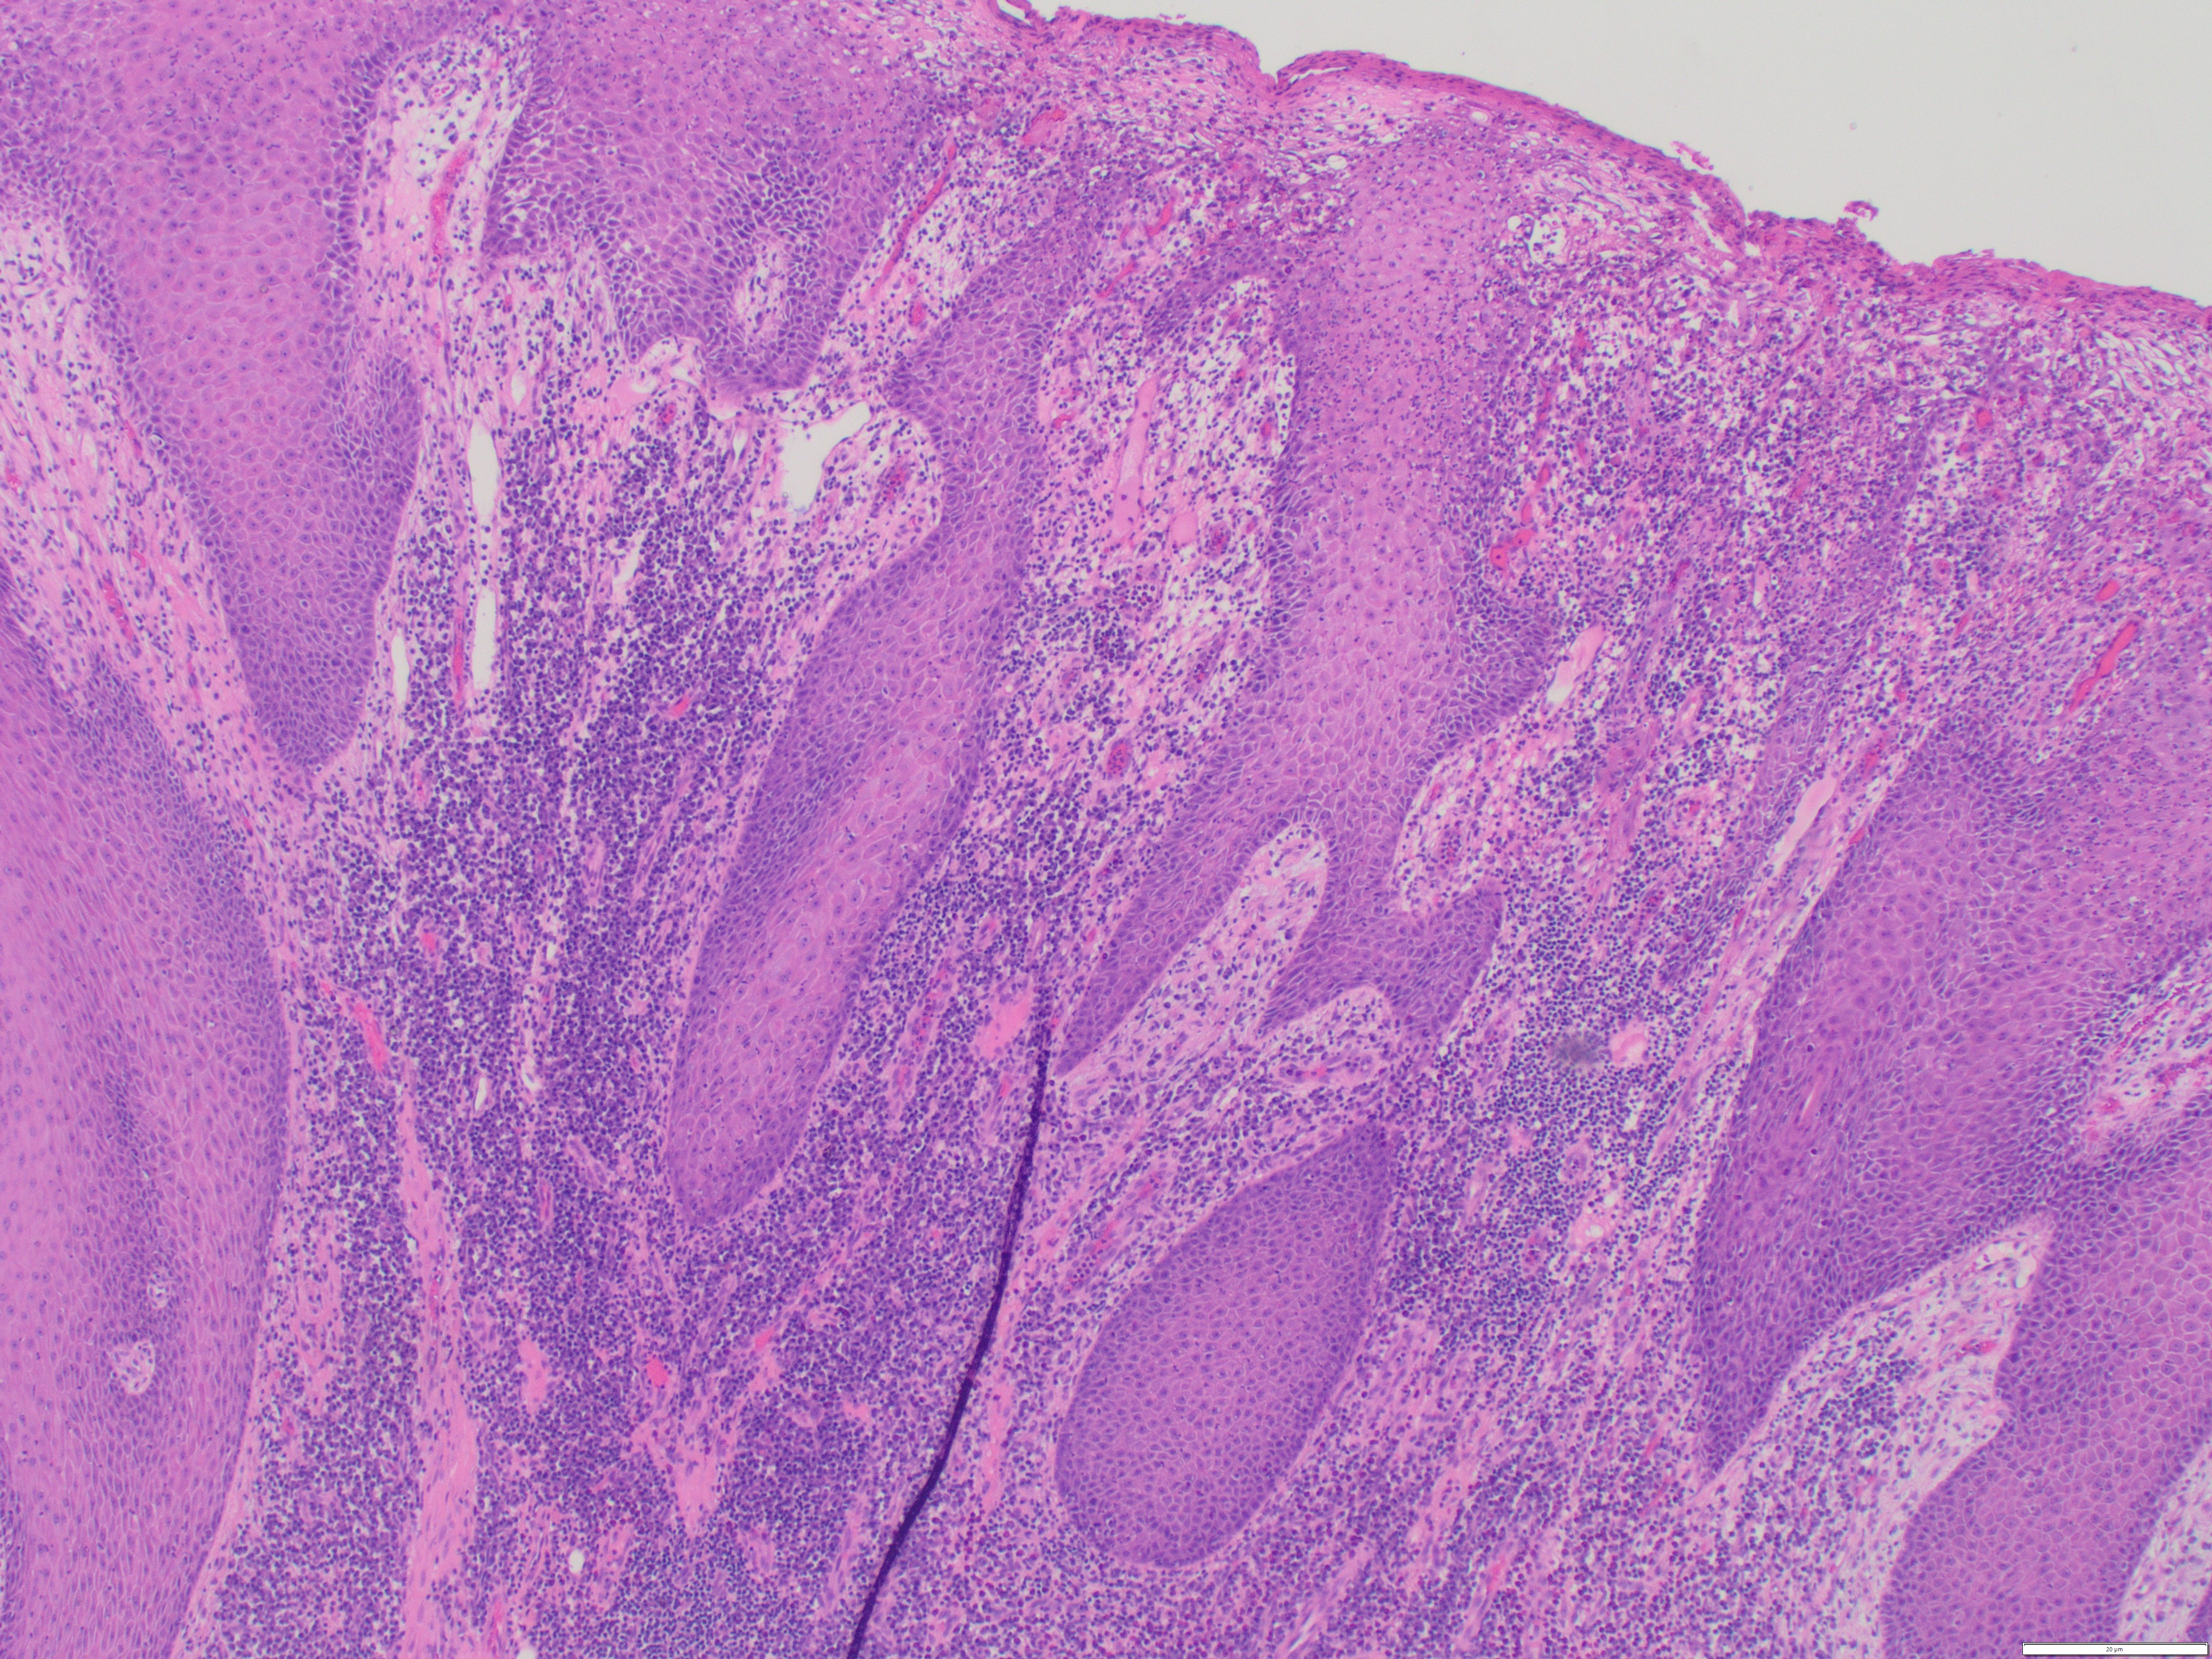

Discussion: Condyloma lata are cutaneous wart-like lesions of the genitalia caused by the spirochete T. pallidum (syphilis). Clinically, these lesions can resemble the more recognized counterpart, HPV-related condyloma acuminatum. However, on histologic examination, Condyloma lata contain epidermal hyperplasia with superficial neutrophils and intense dermal mononuclear cell infiltrate (classically dense plasmacytic inflammation as seen in this case). There is an absence of of the HPV-related koilocytic change, which are typically seen in a condyloma acuminatum.